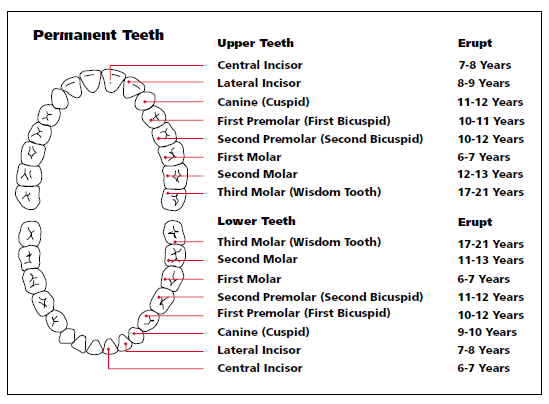

2. dental anatomi gigi permanen ..

2. dental anatomi gigi permanen ..

Berapakah usia maksimum untuk pertumbuhan gigi selepas ia dikeluarkan? - Gigi 2020

Catat! Ini Jadwal Tumbuh dan Tanggal Gigi Si Kecil | theAsianparent Indonesia